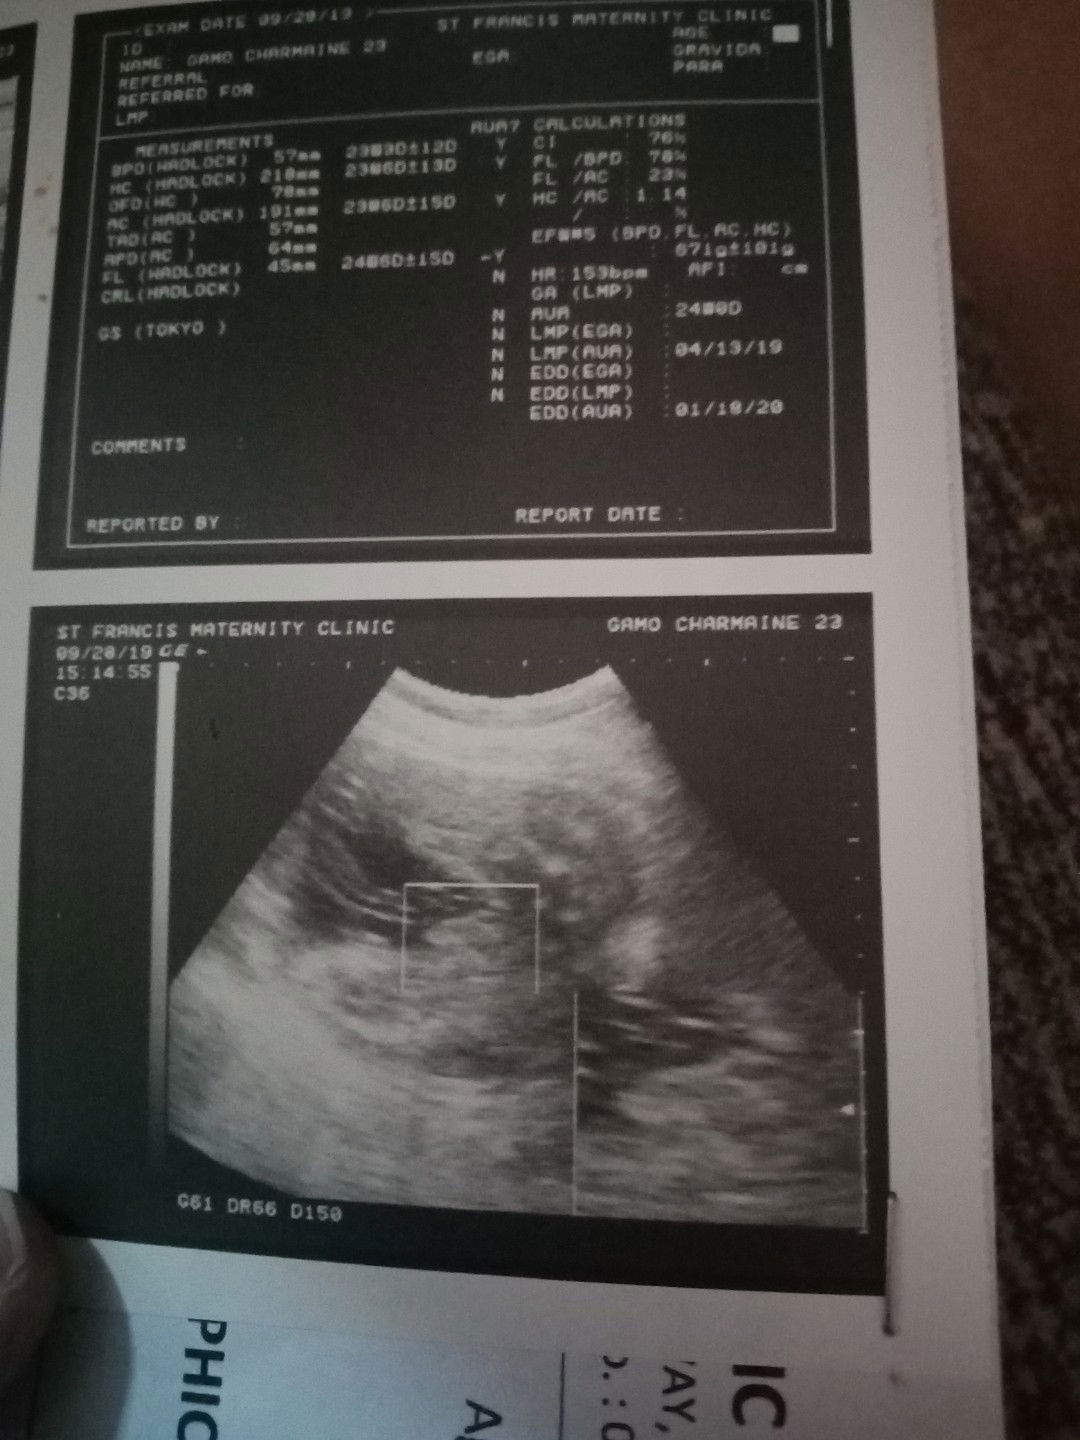

Mga momsh naguguluhan po ako sa due date ko.. LMP ko po kasi ay March 12 onwards di ko po kasi alam exact date pero march 12 na po dineclare.. Sabi ni ob ko nasa 28 weeks na po ako and ang due date ko ay December 17.. Since di naman daw po ako sure sa lmp ko starting dec 15 kabuwanan ko na daw.. Nagpa ultrasound po ako nakaraan, nakalagay dun is 24 wks palang daw ko going 25.. Ano po ba paniniwalaan ko.. Nag aalala po tuloy ako baka maliit masyado si baby.. Edd via lmp Dec 17/ Edd via 1st utz Jan 5/ Edd via 2nd utz Jan 17/